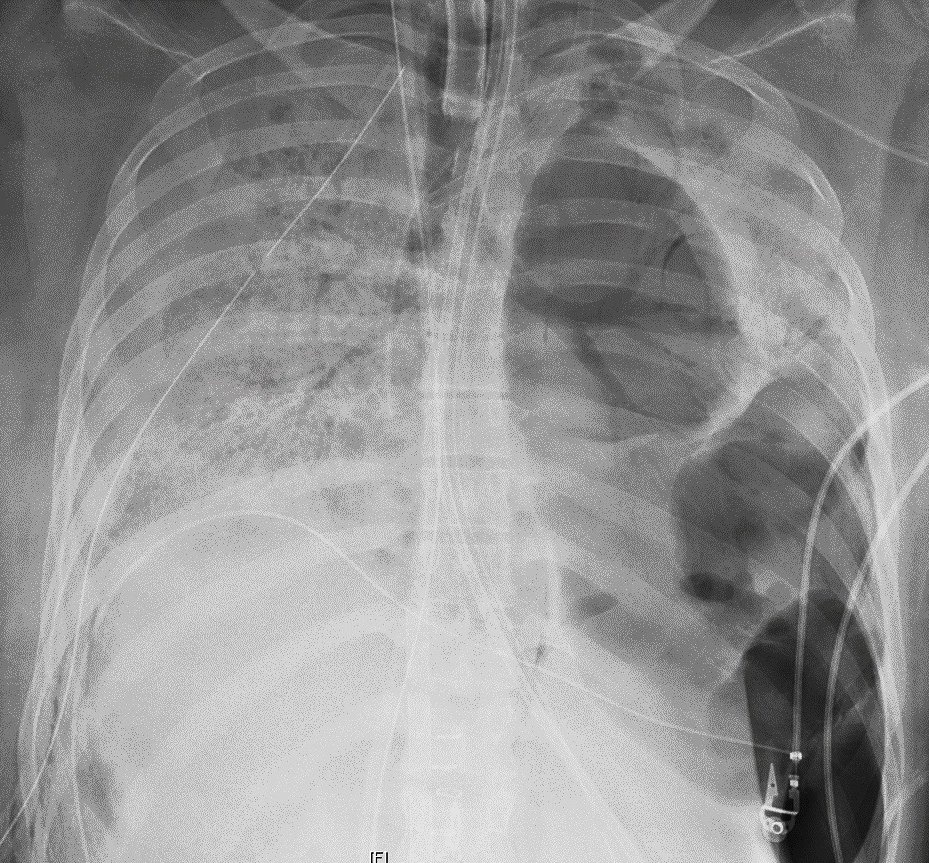

| Hình ảnh chụp X-quang cho thấy phổi bệnh nhân bị thủng nhiều lỗ nhỏ. Ảnh: AP. |

Ca phẫu thuật kéo dài trong 10 tiếng với đầy thách thức, vì virus corona đã khiến phổi của bệnh nhân thủng nhiều lỗ, tới mức phổi gần như dính vào thành ngực, theo bác sĩ Ankit Bharat, người thực hiện ca phẫu thuật.